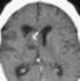

Subependymoma

A subependymoma is a type of brain tumor; specifically, it is a rare form of ependymal tumor. They are usually in middle aged people. [Source: Wikipedia ]

Fourth ventricular lesion

Intraventricular lesion

Lateral ventricle body lesion

T1-hypointense intracranial lesion

T1-isointense intracranial lesion

T2-hyperintense intracranial lesion

Ventricular wall nodule